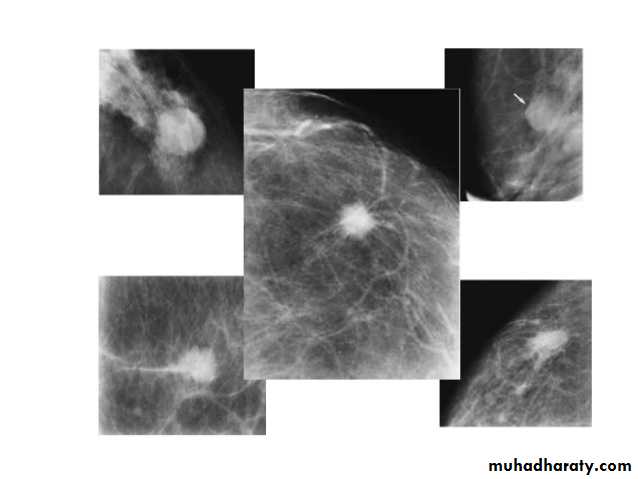

Micro calcifications

Micro calcifications are tiny specks of calcium in the breast. Micro calcifications seen on a mammogram are of more concern than macrocalcifications, but they do not always mean that cancer is present. The shape and layout of microcalcifications help the radiologist judge how likely it is that cancer is present.

In most cases, the presence of microcalcifications does not mean a biopsy is needed. But if the microcalcifications have a suspicious look and pattern, a biopsy will be recommended. (During a biopsy, the doctor removes a small piece of the suspicious area to be looked at under a microscope. A biopsy is the only way to tell if cancer is really present.)

Mammography

Fibroadenomas have a spectrum of features from the well circumscribed discrete oval mass hypo- or isodense to the breast glandular tissue, to a mass with macrolobulation or partially obscured margin. Involuting fibroadenomas in older, typically postmenopausal patients may contain calcification, often producing the classic, coarse popcorn calcification appearance.